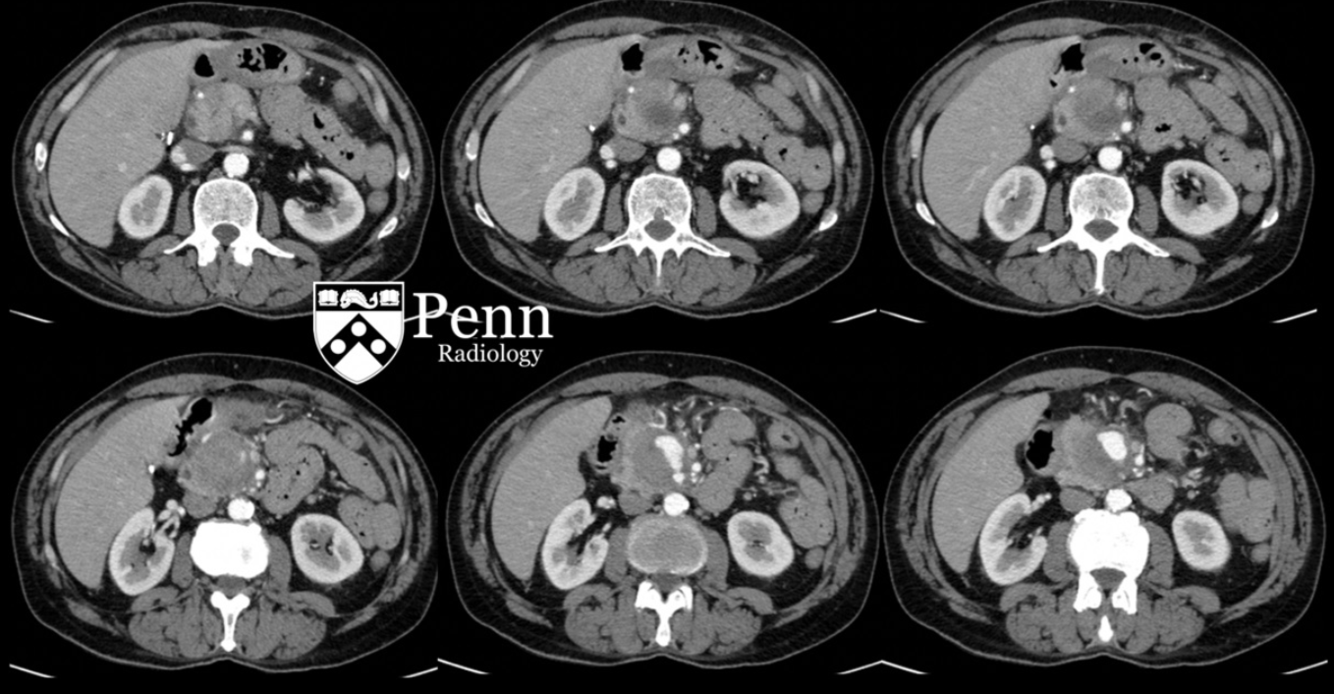

Mulher, 28 anos; dor abdominal.

Mesenterite esclerosante (paniculte, mesenterite retrátil)

Doença crônica idiopática inflamatória da gordura mesentérica. Predomínio em idosos;

Sinal do mesentério enevoado: densificação da gordura com formação de uma pseudocápsula; poupa a gordura ao redor dos vasos do mesentério; pode ter linfonodos mesentéricos aumentados;

Pode estar associado à malignidade como câncer de mama, pulmão, linfoma;

Tratamento inicial envolve corticoterapia; Seguimento envolve queda dos marcadores inflamatórios: PCR, VHS.

60 anos, Dor abdominal;

65 anos, Dor abdominal.

Aumento de PCR e VHS.